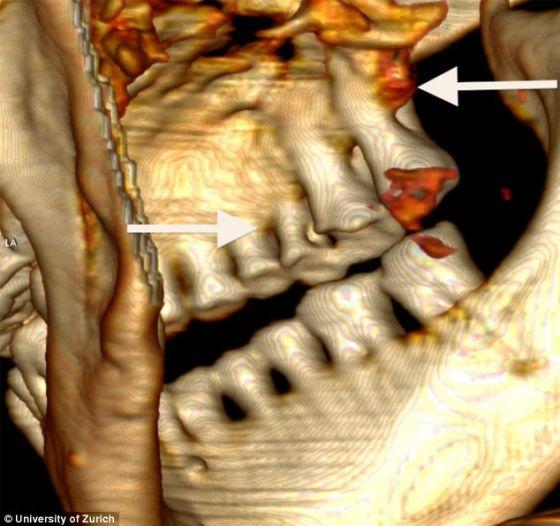

“奥茨”的头骨三维图像,一颗门牙受损严重,其他牙齿也严重磨损,失去了超过一半的牙冠

“奥茨”牙齿的三维图像,右侧箭头所指的位置出现很深的蛀洞,左侧箭头所指的位置臼齿周围骨骼严重受损

研究领导人弗兰克-鲁赫利教授表示“奥茨”出现严重的牙齿磨损,多处出现蛀洞,一颗门齿受损严重,可能由事故所致。虽然对这个冰人的研究已经有20多年历史,但此前从未进行牙齿检查。苏黎世大学进化医学中心的牙医罗杰-塞勒根据最新的X线计算机体层摄影数据对“奥茨”的牙齿进行了检查。X线计算机体层摄影获取了“奥茨”牙齿的三维图像,揭示出“奥茨”的严重口腔问题和重度牙周炎。